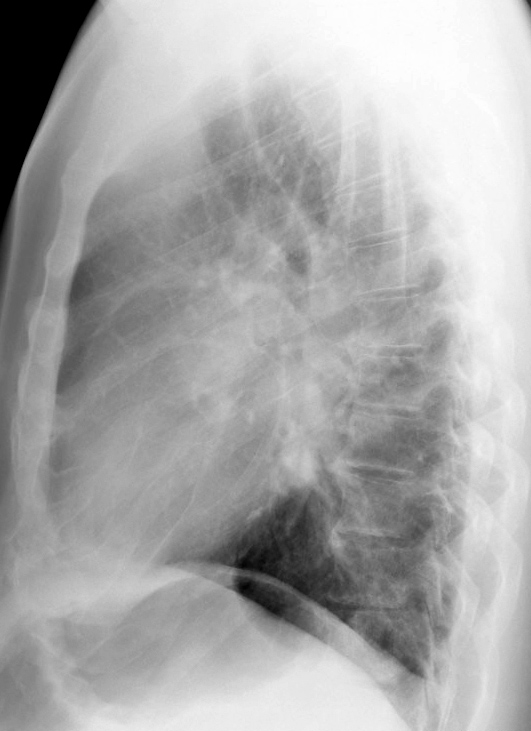

Gallery Congenital Bronch Cyst 1 Lat

Bronch Cyst 1  Lat